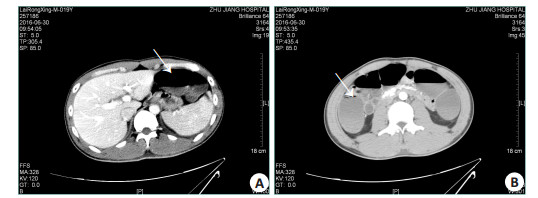

1 资料和方法 1.1 病例资料女性1例,38岁,男性3例,年龄分别为15、19、21岁。病例患者既往身体均健康,无外伤史,无特殊用药史等。因误食自采野生菌汤共约1.5 kg(15、38岁患者各误食约500 mL;19、21岁患者各约250 mL),约8 h后出现腹痛、腹泻和呕吐等症状,24 h后到当地医院行催吐、洗胃、导泻和补液等治疗,3~4 d后因病情急剧加重先后转入我院ICU抢救,其中,38、15岁患者表现为肝肾功能衰竭、重度凝血异常和低血压休克等。转入ICU时开始出现昏迷,格拉斯哥昏迷评分均为3分。血氨浓度分别为78、69 μmol/L。血气分析提示重度代谢性酸中毒,动脉血乳酸水平分别为18、7.7 mmol/L。伴有急性胃肠损伤,血淀粉酶和脂肪酶升高,腹部影像学可见明显的肠道水肿、扩张和积液。另2例为19、21岁男性患者,误食野生菌量减半。临床表现与前者相似,器官功能损害程度轻,未出现神志改变,但急性胃肠损伤程度相对较重,典型影像征象见图 1。此外,4例均伴有横纹肌溶解,表现为乏力、肌肉酸痛、茶色尿和肌酶急剧升高。血肌红蛋白浓度为135~6567 μg/L(中位数2247 μg/L,正常范围20~80 μg/L),血肌酸激酶(CK)水平为315~108 400 U/L(中位数16 820 U/L,正常范围26~140 U/L),血肌酸激酶同工酶(CK-Mb)水平为88~2502 U/L(中位数493 U/L,正常范围0~24 U/L)。4例患者住ICU期间主要的器官功能指标均值(表 1)。

图 1 19岁中毒患者腹部CT影像学改变 Figure 1 Contrast- enhanced abdominal computed tomography images of a 19- year- old patient with poisoning. A: Arrow shows gastric distension and residuals; B: Arrow shows intestinal wall edema, dilation and stasis |